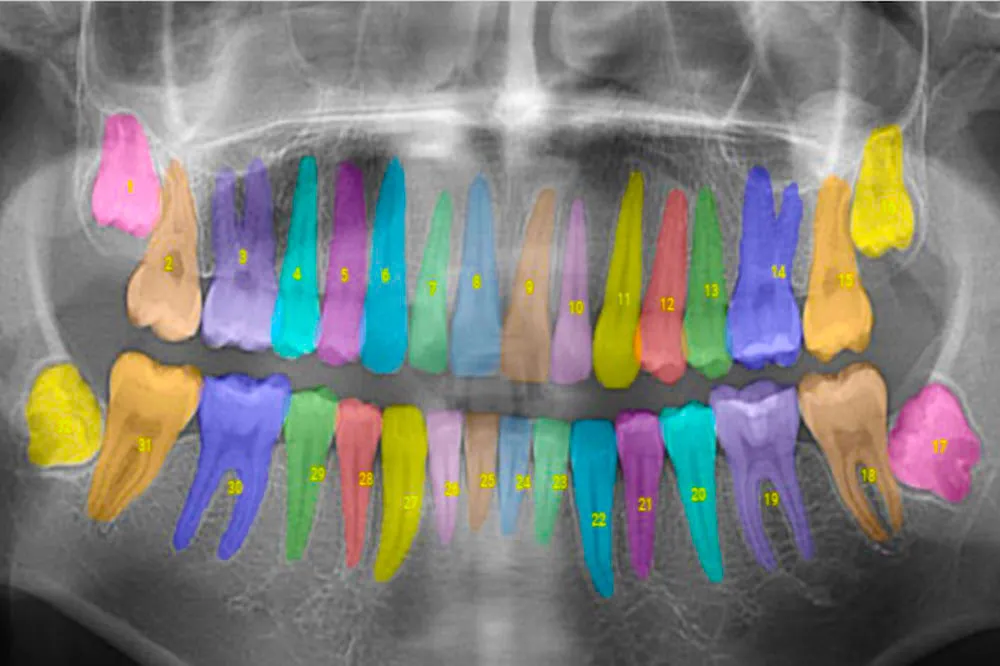

Leading the Way in AI Dentistry: Our Transformative Experience with the Apteryx AI Diagnosing Tool

Introduction Patients throughout Ivy, Charlottesville, and the greater Albemarle County area trust Willis & Associates Family Dentistry Ivy for expert...